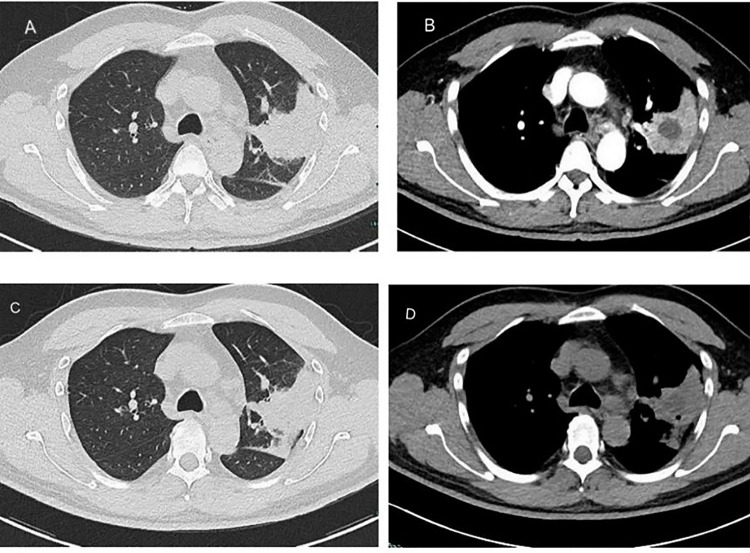

Results: All patients had oral diseases, and 75% were long-term smokers. The primary clinical manifestations were nonspecific respiratory symptoms, including cough, fever, chest pain, and hemoptysis. Chest CT revealed consolidation and cavitation in the upper lobes of the lungs. T. forsythia was successfully detected by mNGS of BALF, while conventional cultures failed to identify pathogens in all cases. All patients received combination antibiotic therapy based on metronidazole and piperacillin-tazobactam, with some cases requiring additional antibiotics. Following treatment, significant clinical improvement was observed, and follow-up imaging demonstrated gradual resolution of the lesions.